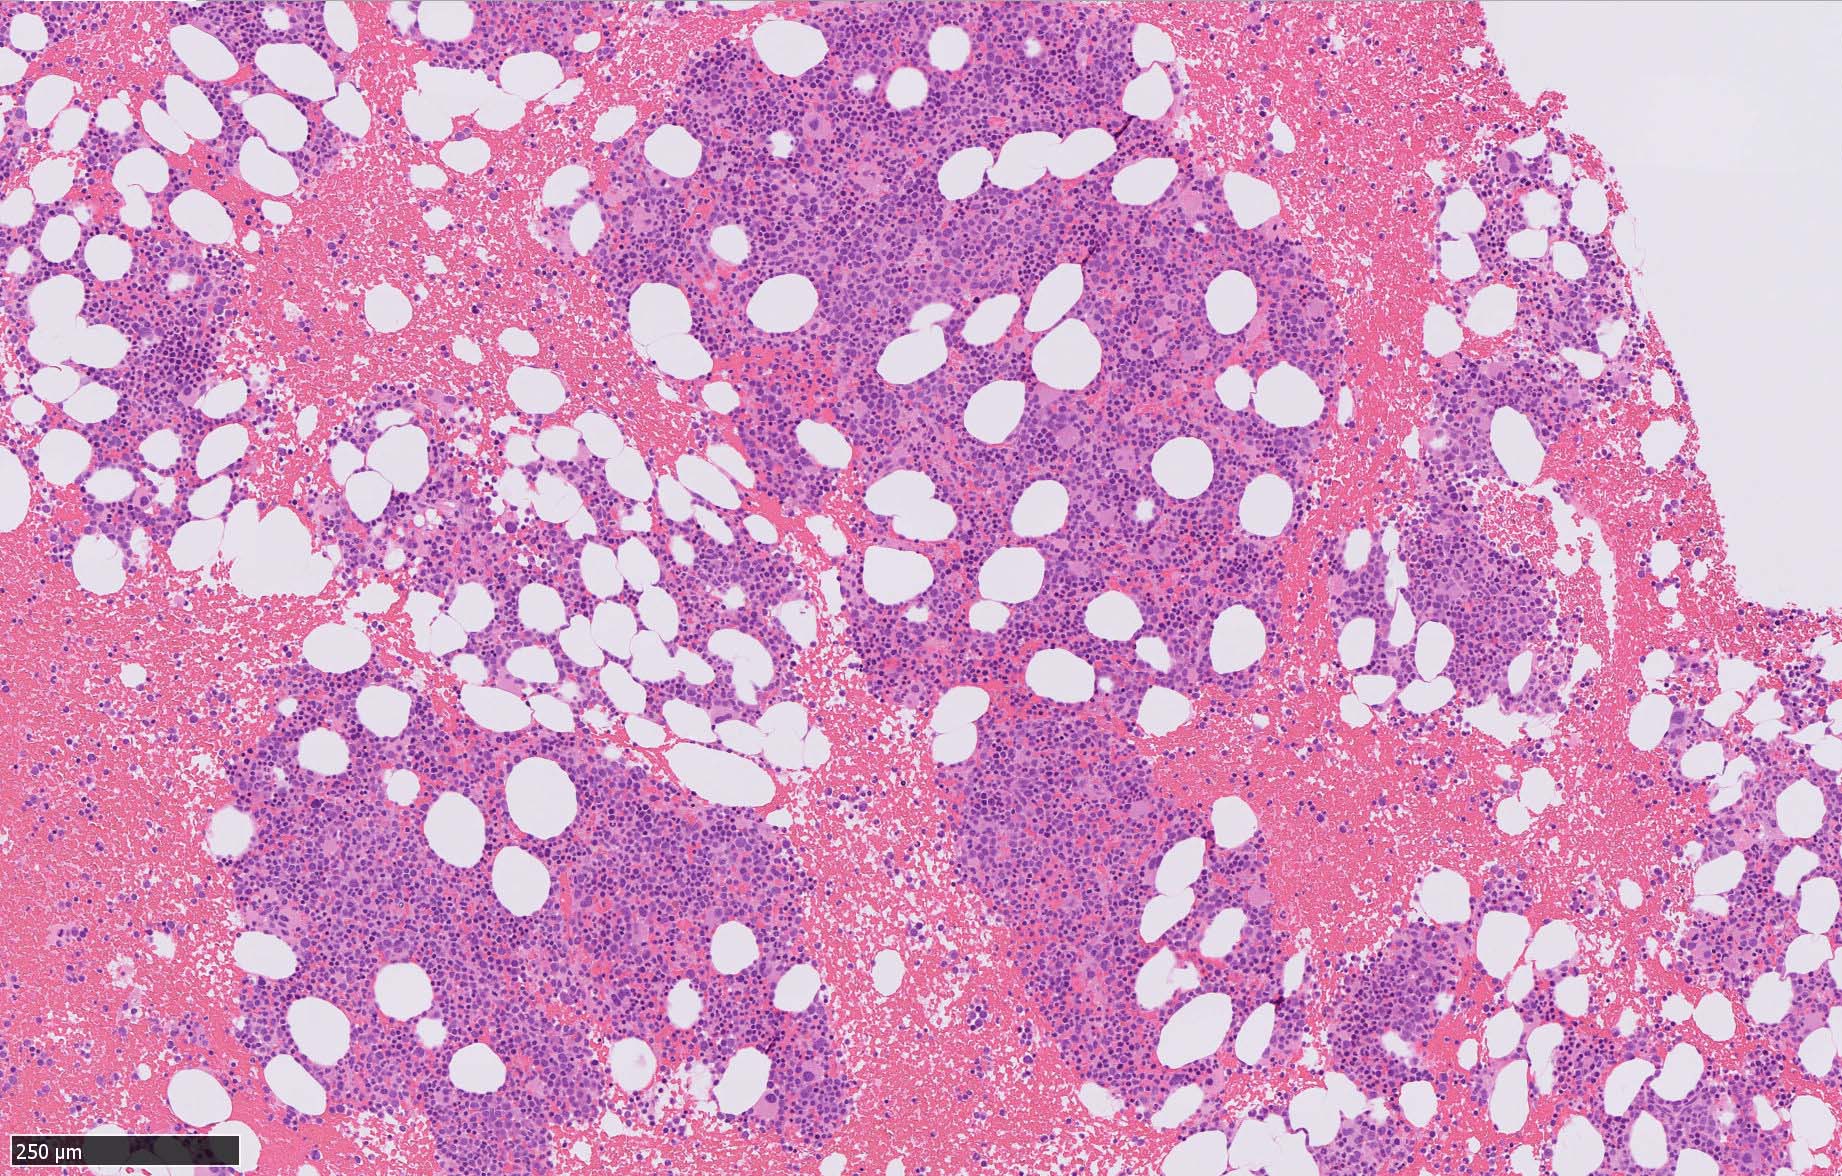

骨髄病理所見

HEでは腫瘍細胞の同定が難しい. 本症例は ASD-Giemsa染色を見ても, 腫瘍胞巣はよくわからなかった. 皮膚が先に診断がつき, 次いでBone marrowだったため, 免疫染色にすすめたが, Bone marrowが先だと診断に困ったかもしれない. 本例は, 骨髄がhypercellularで, dysplastic hematopoiesisがありMDSも疑われている.

免疫染色

CD4は染まりすぎの感がある(濃く染まる細胞はCD4+ T-cellかもしれない). CD56, CD123が陽性で可能性が高くなり, BPDCNの診断にはCD34は陰性であることが必要

TCF4、CD123、TCL1をconsultationにより染色していただき, 陽性を確認した. CD34-, lysozyme-, CD123(おいてある病院は少ないかも)をしらべて, BPDCN研究会あてconsultationをする流れでしょうか.

BPDCN骨髄病変の病理

症例骨髄に認められた異形成造血所見

Mgkは低分葉, 円形単核の細胞が多く, 分離円形核のMgkもみられた. 赤芽球はproerythroblstsのみの小集簇や孤在性出現あり. 成熟赤芽球が乏しい. 顆粒球系細胞も分葉好中球への分化像が少ない.

免疫染色では, HbFを発現する赤芽球の集簇巣が散見しているほか, p53陽性細胞が軽度に増加している. CD34陽性細胞増加はなし.CD42b染色でmicroMgkはみられなかった. 異形成造血が強く疑われる.